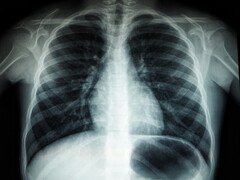

Naukowcy donoszą, że tylko jedna sesja stylizacji włosów trwająca 10-20 minut może skutkować wdychaniem ponad 10 miliardów nanocząstek. Mówią, że ten poziom zanieczyszczenia jest porównywalny z tym, co można uzyskać w środku gęstego ruchu na autostradzie. Biorąc pod uwagę rozmiar tych cząstek, mogą one łatwo przenikać głęboko do płuc. Może to prowadzić do problemów zdrowotnych, takich jak stres oddechowy, zapalenie płuc i pogorszenie funkcji poznawczych.